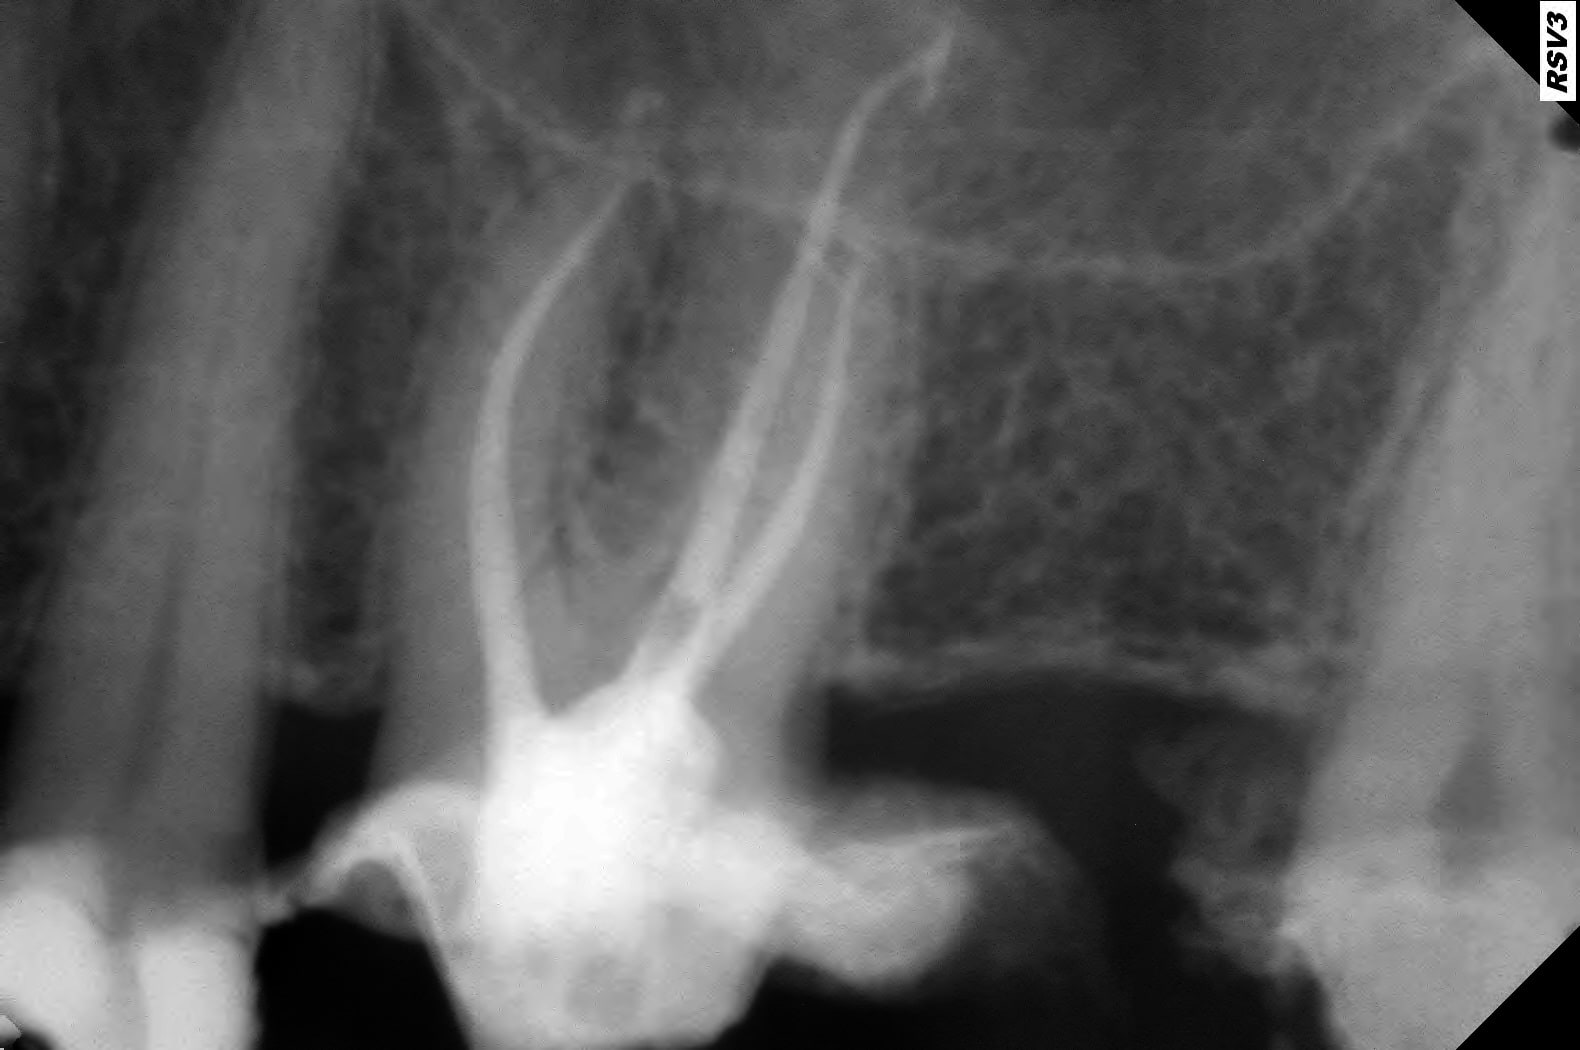

J'ai fait un conebeam de la 26.

L'obturation des racines est correcte, il y a juste une petite image apicale au niveau de la racine palatine avec un léger dépassement de pâte.

Pas de coupes horizontales ?

Le MV2 non obturé ici peut parfois, selon sa configuration, causer des douleurs variées.

Je peux me tromper, les coupes ne sont pas idéales pour conclure ☝️

Pour répondre à Dentarue: je viens de faire des coupes horizontale et centrées sur la racine vestibulaire en tournant autour d'un potentiel MV2. La gutta et le ciment font un joli artefact radio donc ce n'est pas concluant.

On le voit très bien sur ta 3d.

Aucune gloire, on ne voit que ça.

Chercher une deuxième entrée en vestibulaire quand on voit sur cette coupe et sur la coupe horizontale que c’est le palatin qui n’est pas obturé, … les mots me manquent.

Il cherche en vestibulaire de MV mais c’est en palatin de MV qu’il fallait chercher, cela me semblait aller sans dire ☝️

Tout est sur la 3d.

Le MV2 n’est pas très proche de la furcation mais plutôt plus mésial que le MV1. Il est très visible à la radio et ne doit pas être bien compliqué à traiter, mais pour ça il faut s’en donner les moyens et ça commence par la digue.

Tu nous dis qu’il n’y a pas de MV2 et tu nous montres des coupes où il saute aux yeux puis tu vois la patiente entre deux pour désobturer MV1 sans digue… et laisser MV2 non traité…